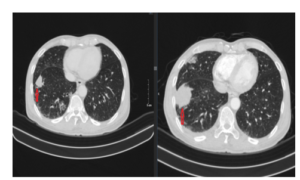

Case lâm sàng: Ứng dụng trí tuệ nhân tạo (Artificial intelligence – AI) trong chẩn đoán và điều trị sớm Ung thư phổi tại Trung tâm Y học hạt nhân và Ung bướu, Bệnh viện Bạch Mai

Case lâm sàng: Ứng dụng trí tuệ nhân tạo (Artificial intelligence – AI) trong chẩn đoán và điều trị sớm Ung thư phổi tại Trung tâm Y học hạt nhân và Ung bướu, Bệnh viện Bạch Mai GS.TS. Mai Trọng Khoa, PGS.TS. Phạm Cẩm Phương, BSNT Nguyễn Ngọc Ánh...